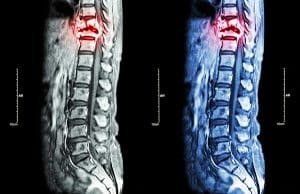

When you suffer from a nervous system injury like one to your spinal cord or brain, it will impact your sensory and motor neurons. The nervous system is very complex; therefore it is necessary to have specialists review your injury and diagnose your condition. The spinal cord sections that often lead to spasticity are the cervical or thoracic, which are higher up on the spine. To diagnose spasticity and determine the type, you will need to get a full medical assessment that will include the following steps:

- An MRI or CT or both